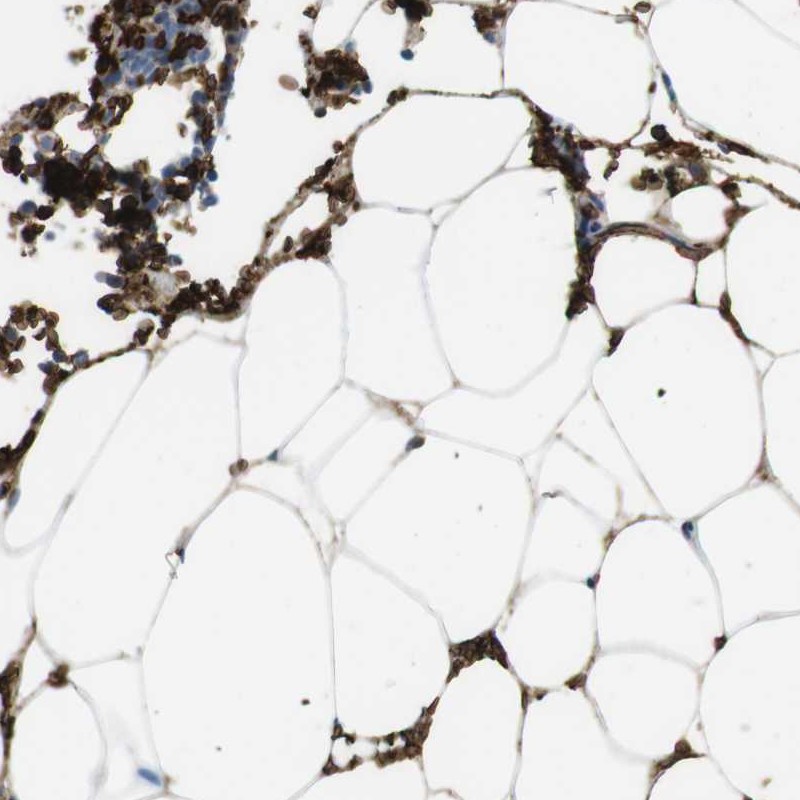

Immunohistochemistry analysis in human bone marrow and cerebral cortex tissues using Anti-SLC4A1 antibody. Corresponding SLC4A1 RNA-seq data are presented for the same tissues.